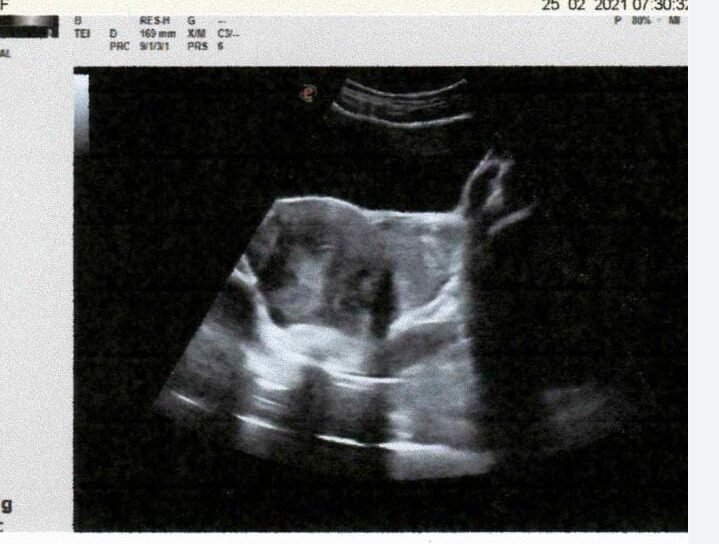

CASE STUDIES

Real-Life Success Stories and Medical Breakthroughs

INTRODUCTION: ECTOPIC PREGNANCY OCCURS WHEN A F...